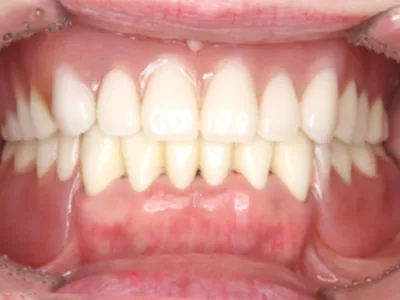

after

主訴入れ歯がくちゃくちゃして噛めない

治療内容被せ物(メタルボンド)保険外の義歯(ミリングギシ)

治療期間1年

費用1,100,000円(税込)(義歯と被せ物代合わせて)

リスク・副作用義歯なので着脱が必要です。仮の義歯を作る場合があります。